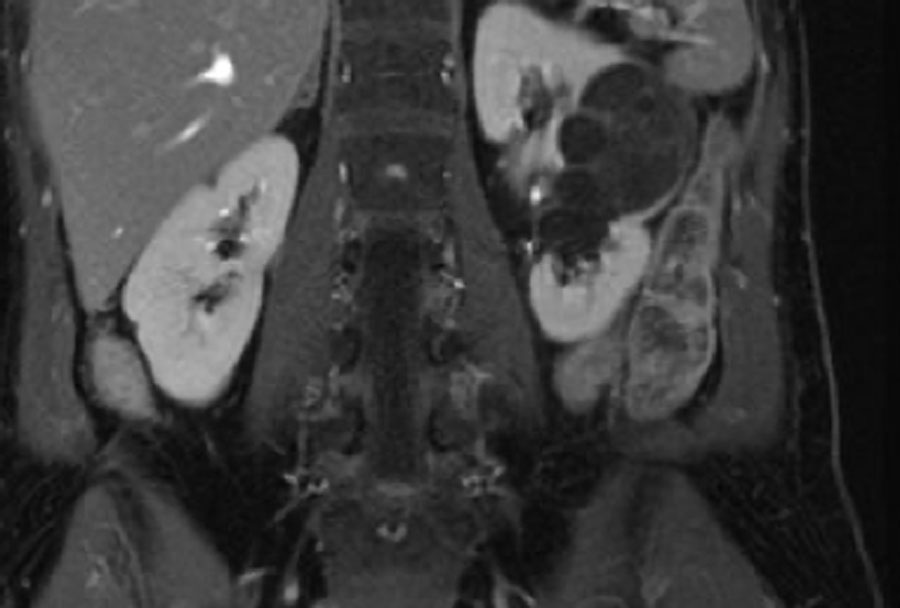

Ảnh T2W mặt phẳng axial và ảnh T1W mặt phẳng coronal có bão hòa mỡ và tiêm Gadolinium.

Có một khối dạng nang ở thận trái với nhiều vách ngăn mỏng ngấm thuốc.

Tổn thương được phân loại là Bosniak IIF.